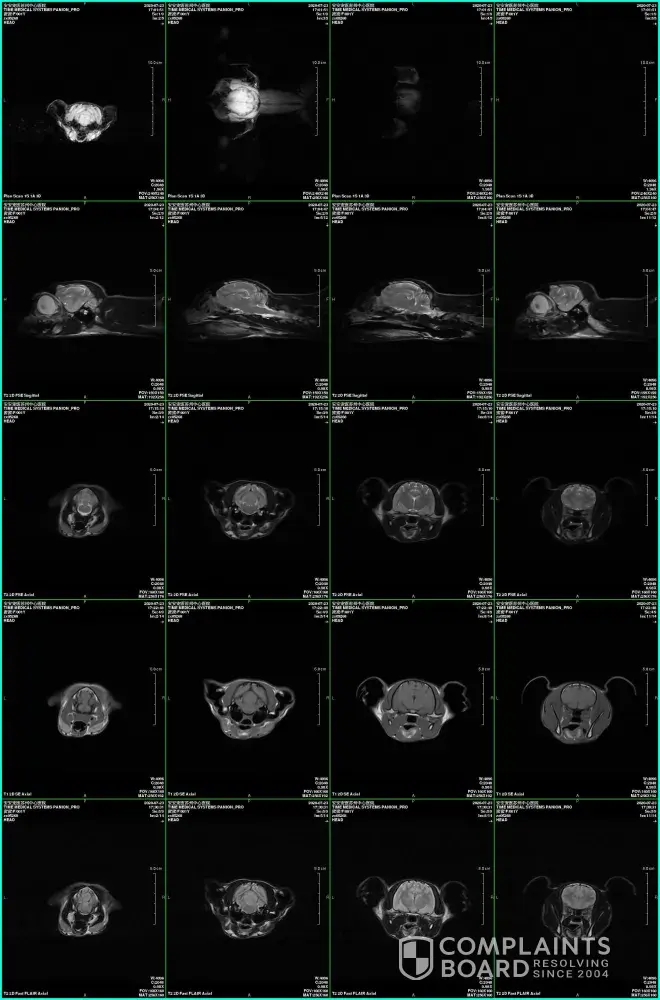

Starlite Rags Ragdoll cat with primary epilepsy

Hi everyone, please think carefully before you adopt a lovely ragdoll from this cattery. She might have PRIMARY EPILEPSY!!! Me and my boyfriend adopted Misty, a lovely chocolate bicolor ragdoll girl, from Starliterags last November and everything was fine until Misty turned to 1 year old. On July 22, Misty had her first sudden seizure and it caused her to...